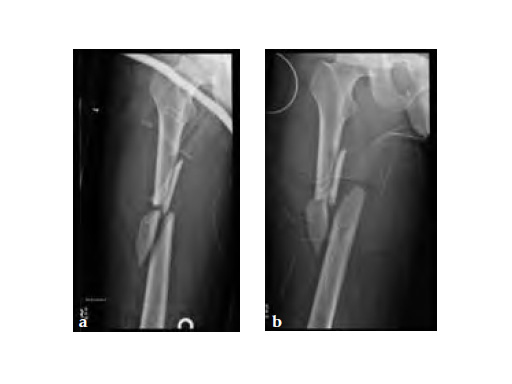

Besides severe upper limb injuries, maxillofacial injuries, a lateral compression pelvic ring injury, and pulmonary contusions, the patient sustained a 32-C3 femur fracture right.

After initial stabilization with an external fixator, the femur was nailed in a closed fashion stabilized with an AFN2 in static mode. The accurate length of the injured femur was contemplated from the uninjured leg.